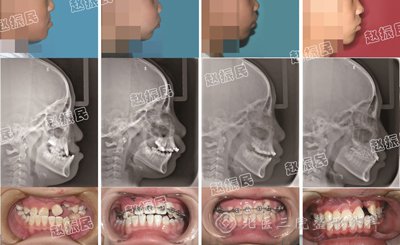

该技术的治疗效果展示:

术前术后影象拟合:术前(绿色部分) 术后(红色部分),表明术后面中部骨骼整体三维生长